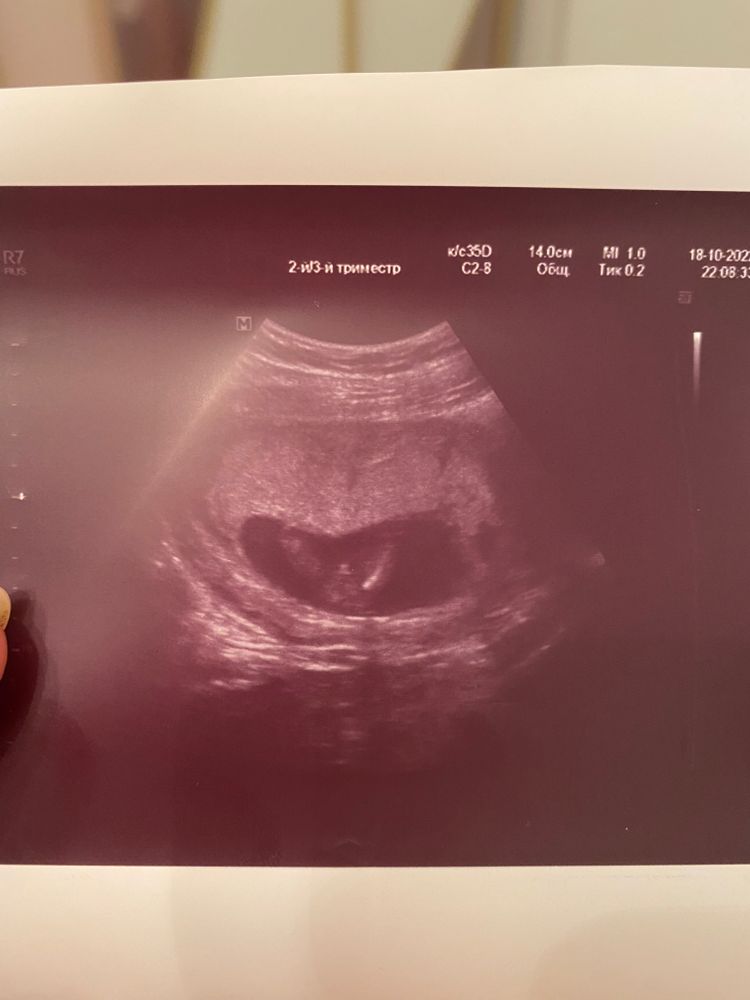

Пол по узи)

скорее всего да.на фото мы видим ножки малыша, а между ног ... сами понимаете) мне кажется, достаточно четко видно, не исключаю, что ошибаюсь

Виктория, посмотрим, как будет дальше) между ног хорошо видно, согласна с вами)

Скрининг в 12 недель, кого видите ?) Сходила на узи определения пола )